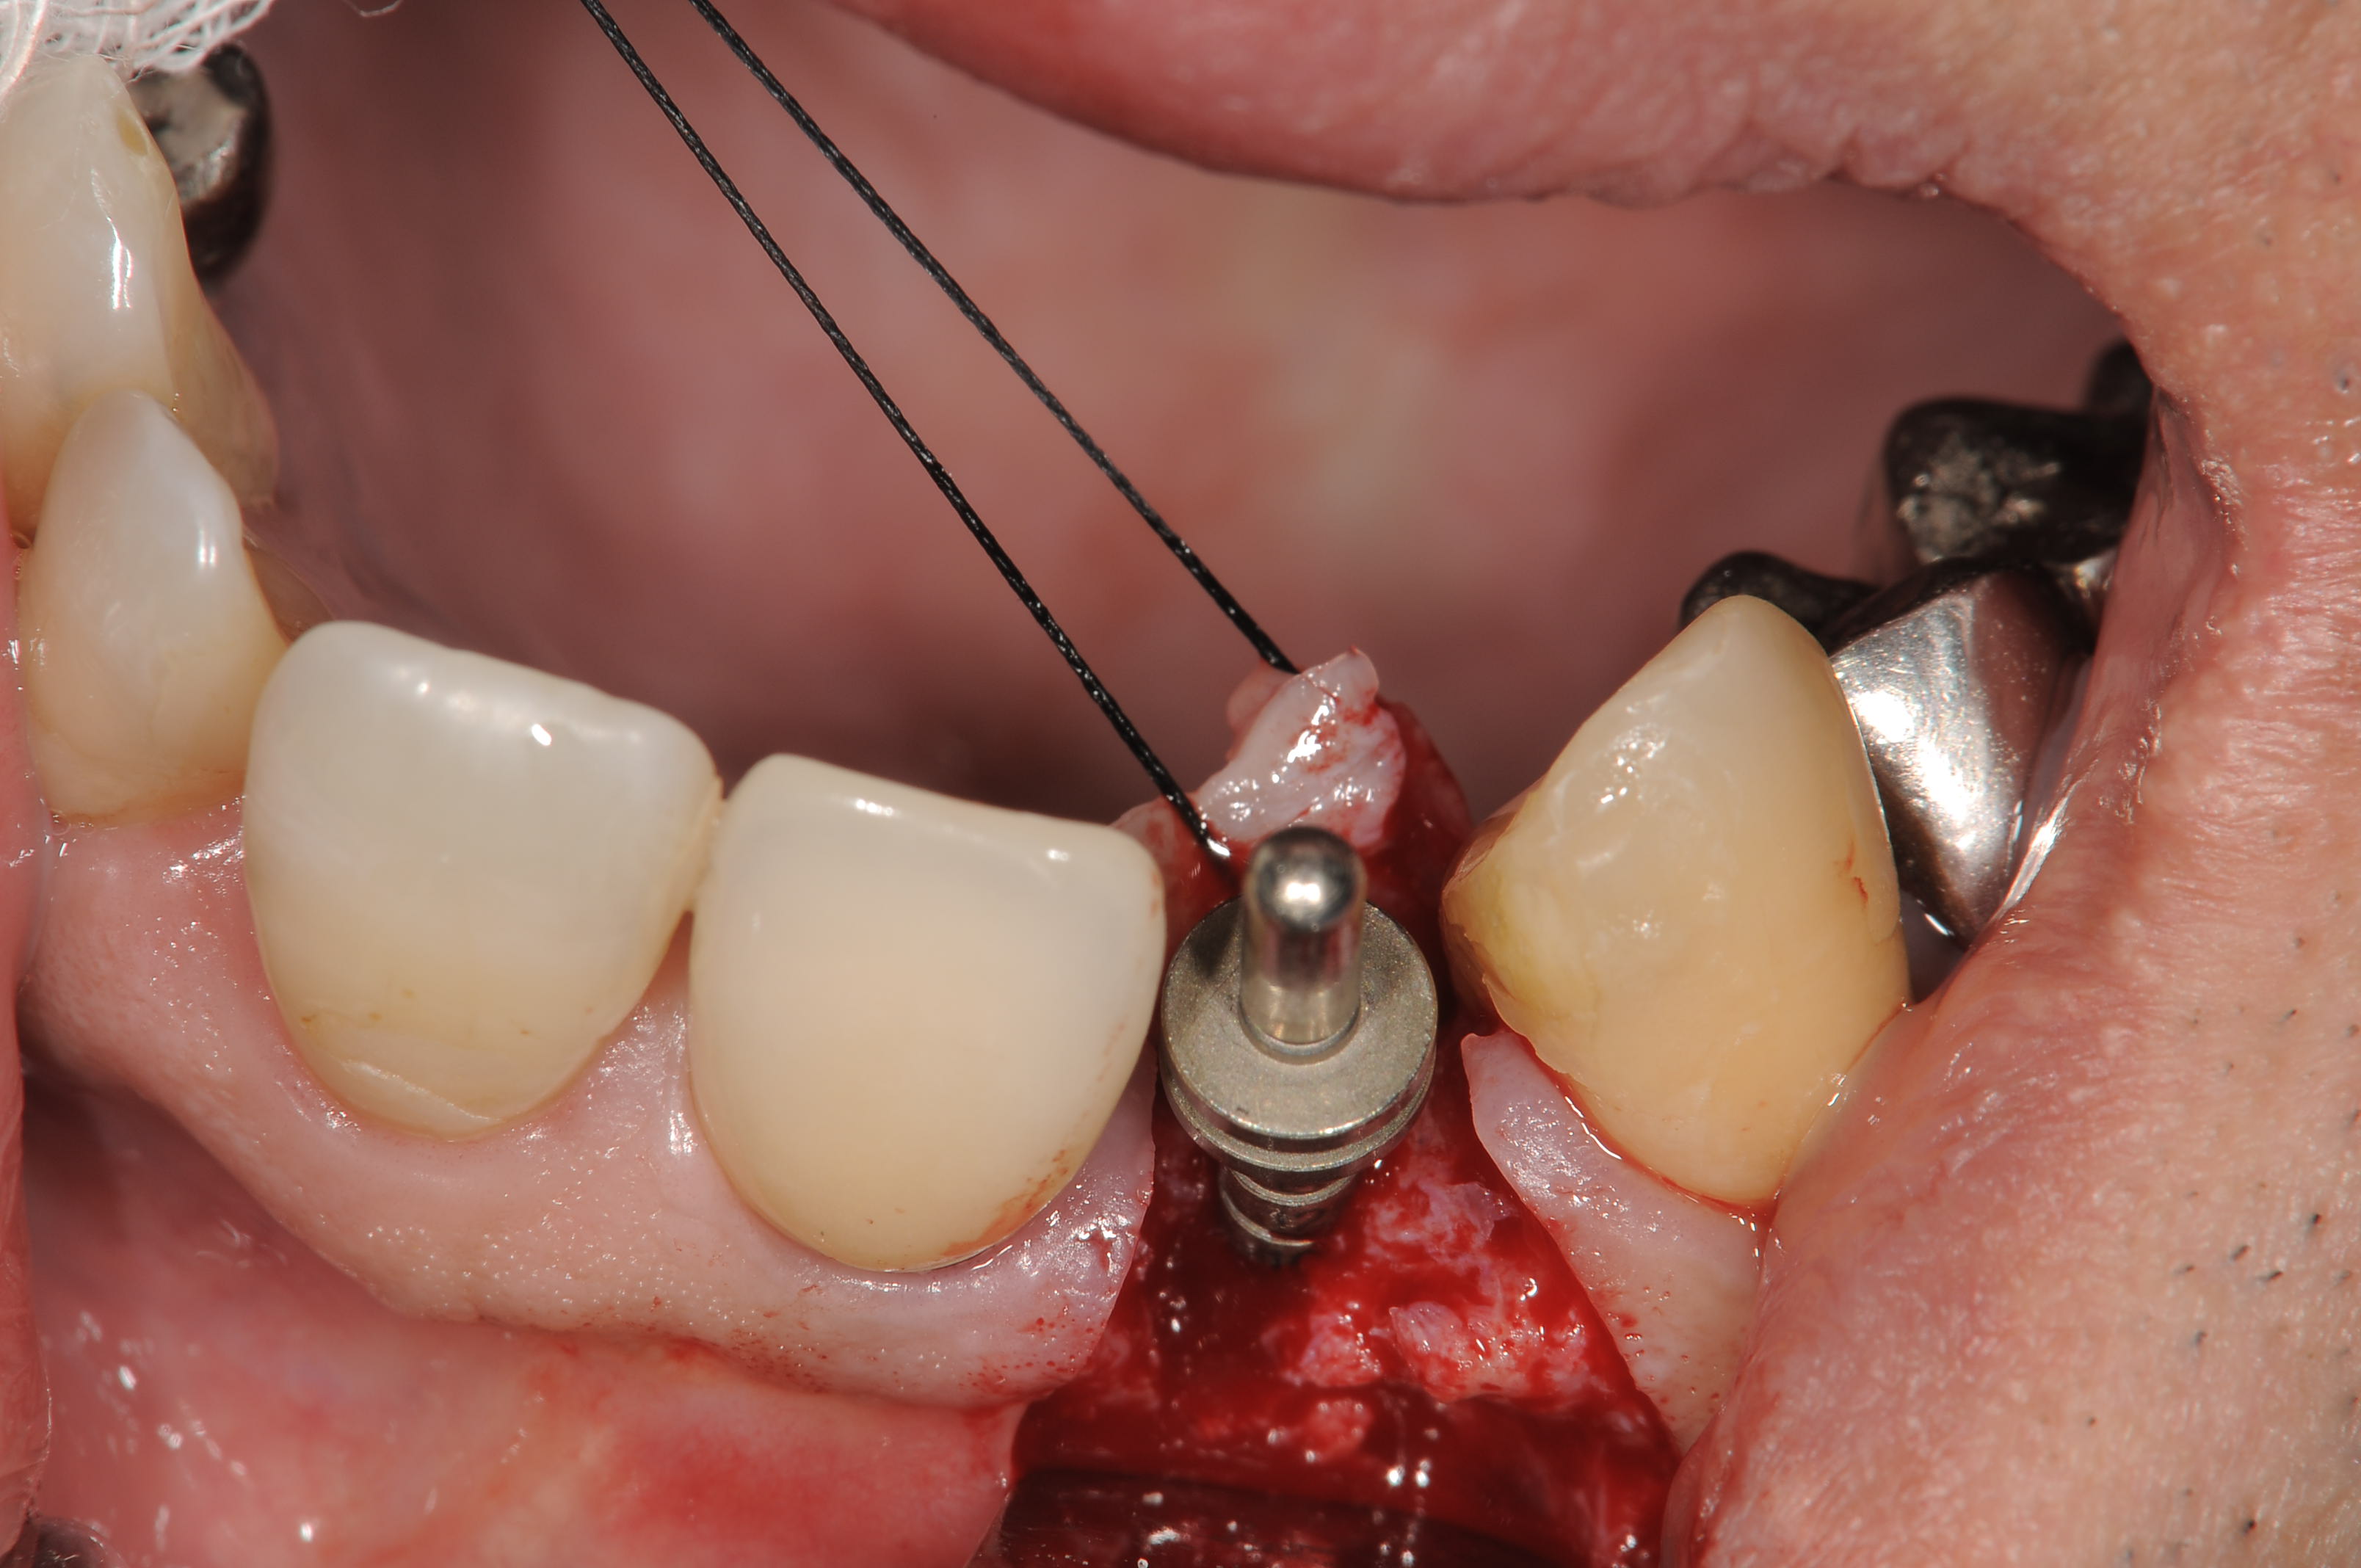

埋入位置の確認をしています。